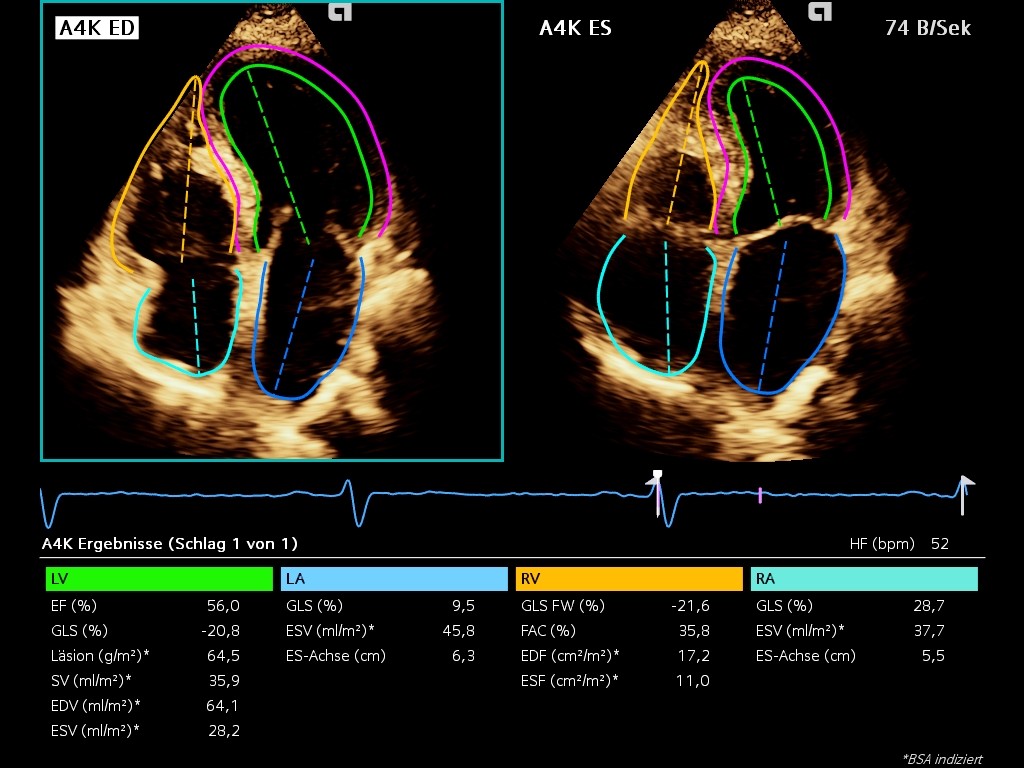

Loop: LASct -2.6%, LASr 11% / Image: RASr 28.7%

Atrial Stunning & elevation of filling pressures of the LA 3 days after CV, already borderline normal RA Strain